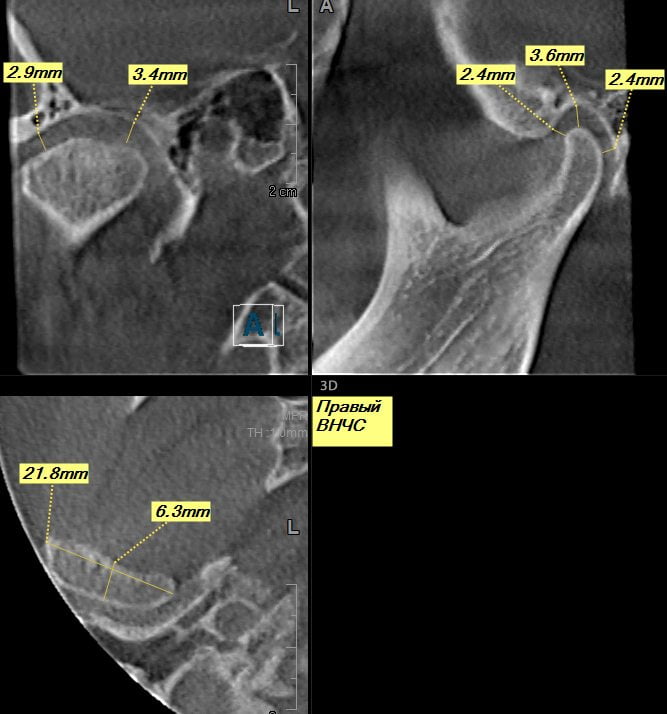

При выборе методов лечения врач учитывает вид заболевания, стадию его течения, степень повреждения костных, хрящевых, мягких тканей. Для восстановления функциональной активности височно-нижнечелюстного сустава (ВНЧС) чаще проводится консервативная терапия. При ее неэффективности пациент готовится к хирургическому вмешательству.

Остеоартроз ВНЧС – хроническая патология, вызванная дистрофическими процессами в тканях сустава. Для нее характерно постепенное разрушение хрящевых тканей и формирование костных разрастаний (остеофитов). В результате истончения хрящей и уменьшения выработки синовиальной жидкости функциональная активность сустава существенно снижается. Во время переживания пищи или разговора возникают болезненные ощущения. При движении челюстью слышатся хруст, щелчки. В утренние часы сустав опухает, но в течение дня отечность исчезает из-за выработки в организме особых гормоноподобных веществ. После сна ощущается некоторая скованность движений, тугоподвижность сочленения.

Примерно спустя полгода ограничивается амплитуда движений ВНЧС, наблюдается тугоподвижность, больной при открывании рта непроизвольно смещает челюсть в одну сторону. В области, пораженной остеоартрозом, ощущается онемение и покалывание кожи. Возникают головные, ушные, глазные боли. Иногда человек с остеоартрозом обращается к отоларингологу с жалобами на снижение слуха. Нередко пациенты интересуются у врачей, почему болит челюстной сустав и челюсть больно открывать. Нередко это указывает на развитие анкилоза — полного или частичного сращения суставной щели.